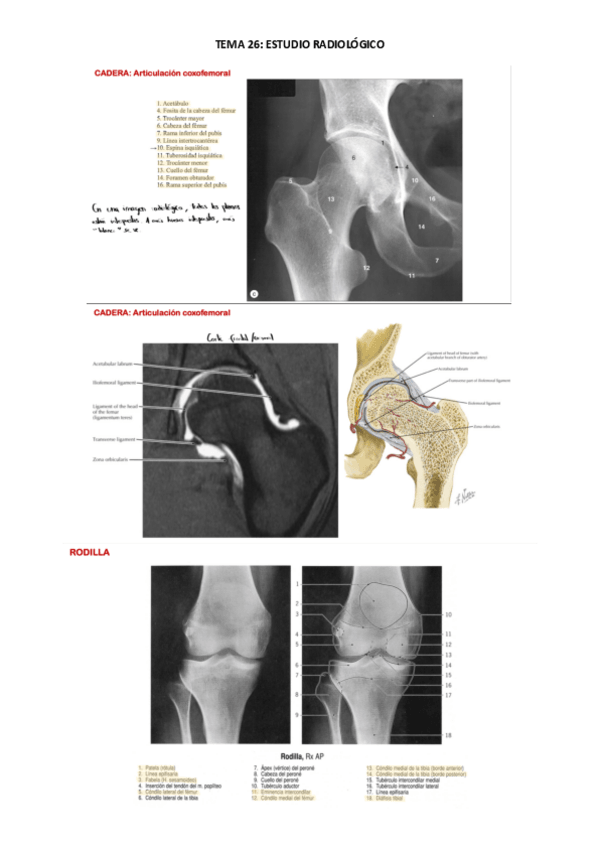

He publicado nuevos apuntes de 2º Anatomía EE.II.: TEMA-26-anatomia-mmii.pdf